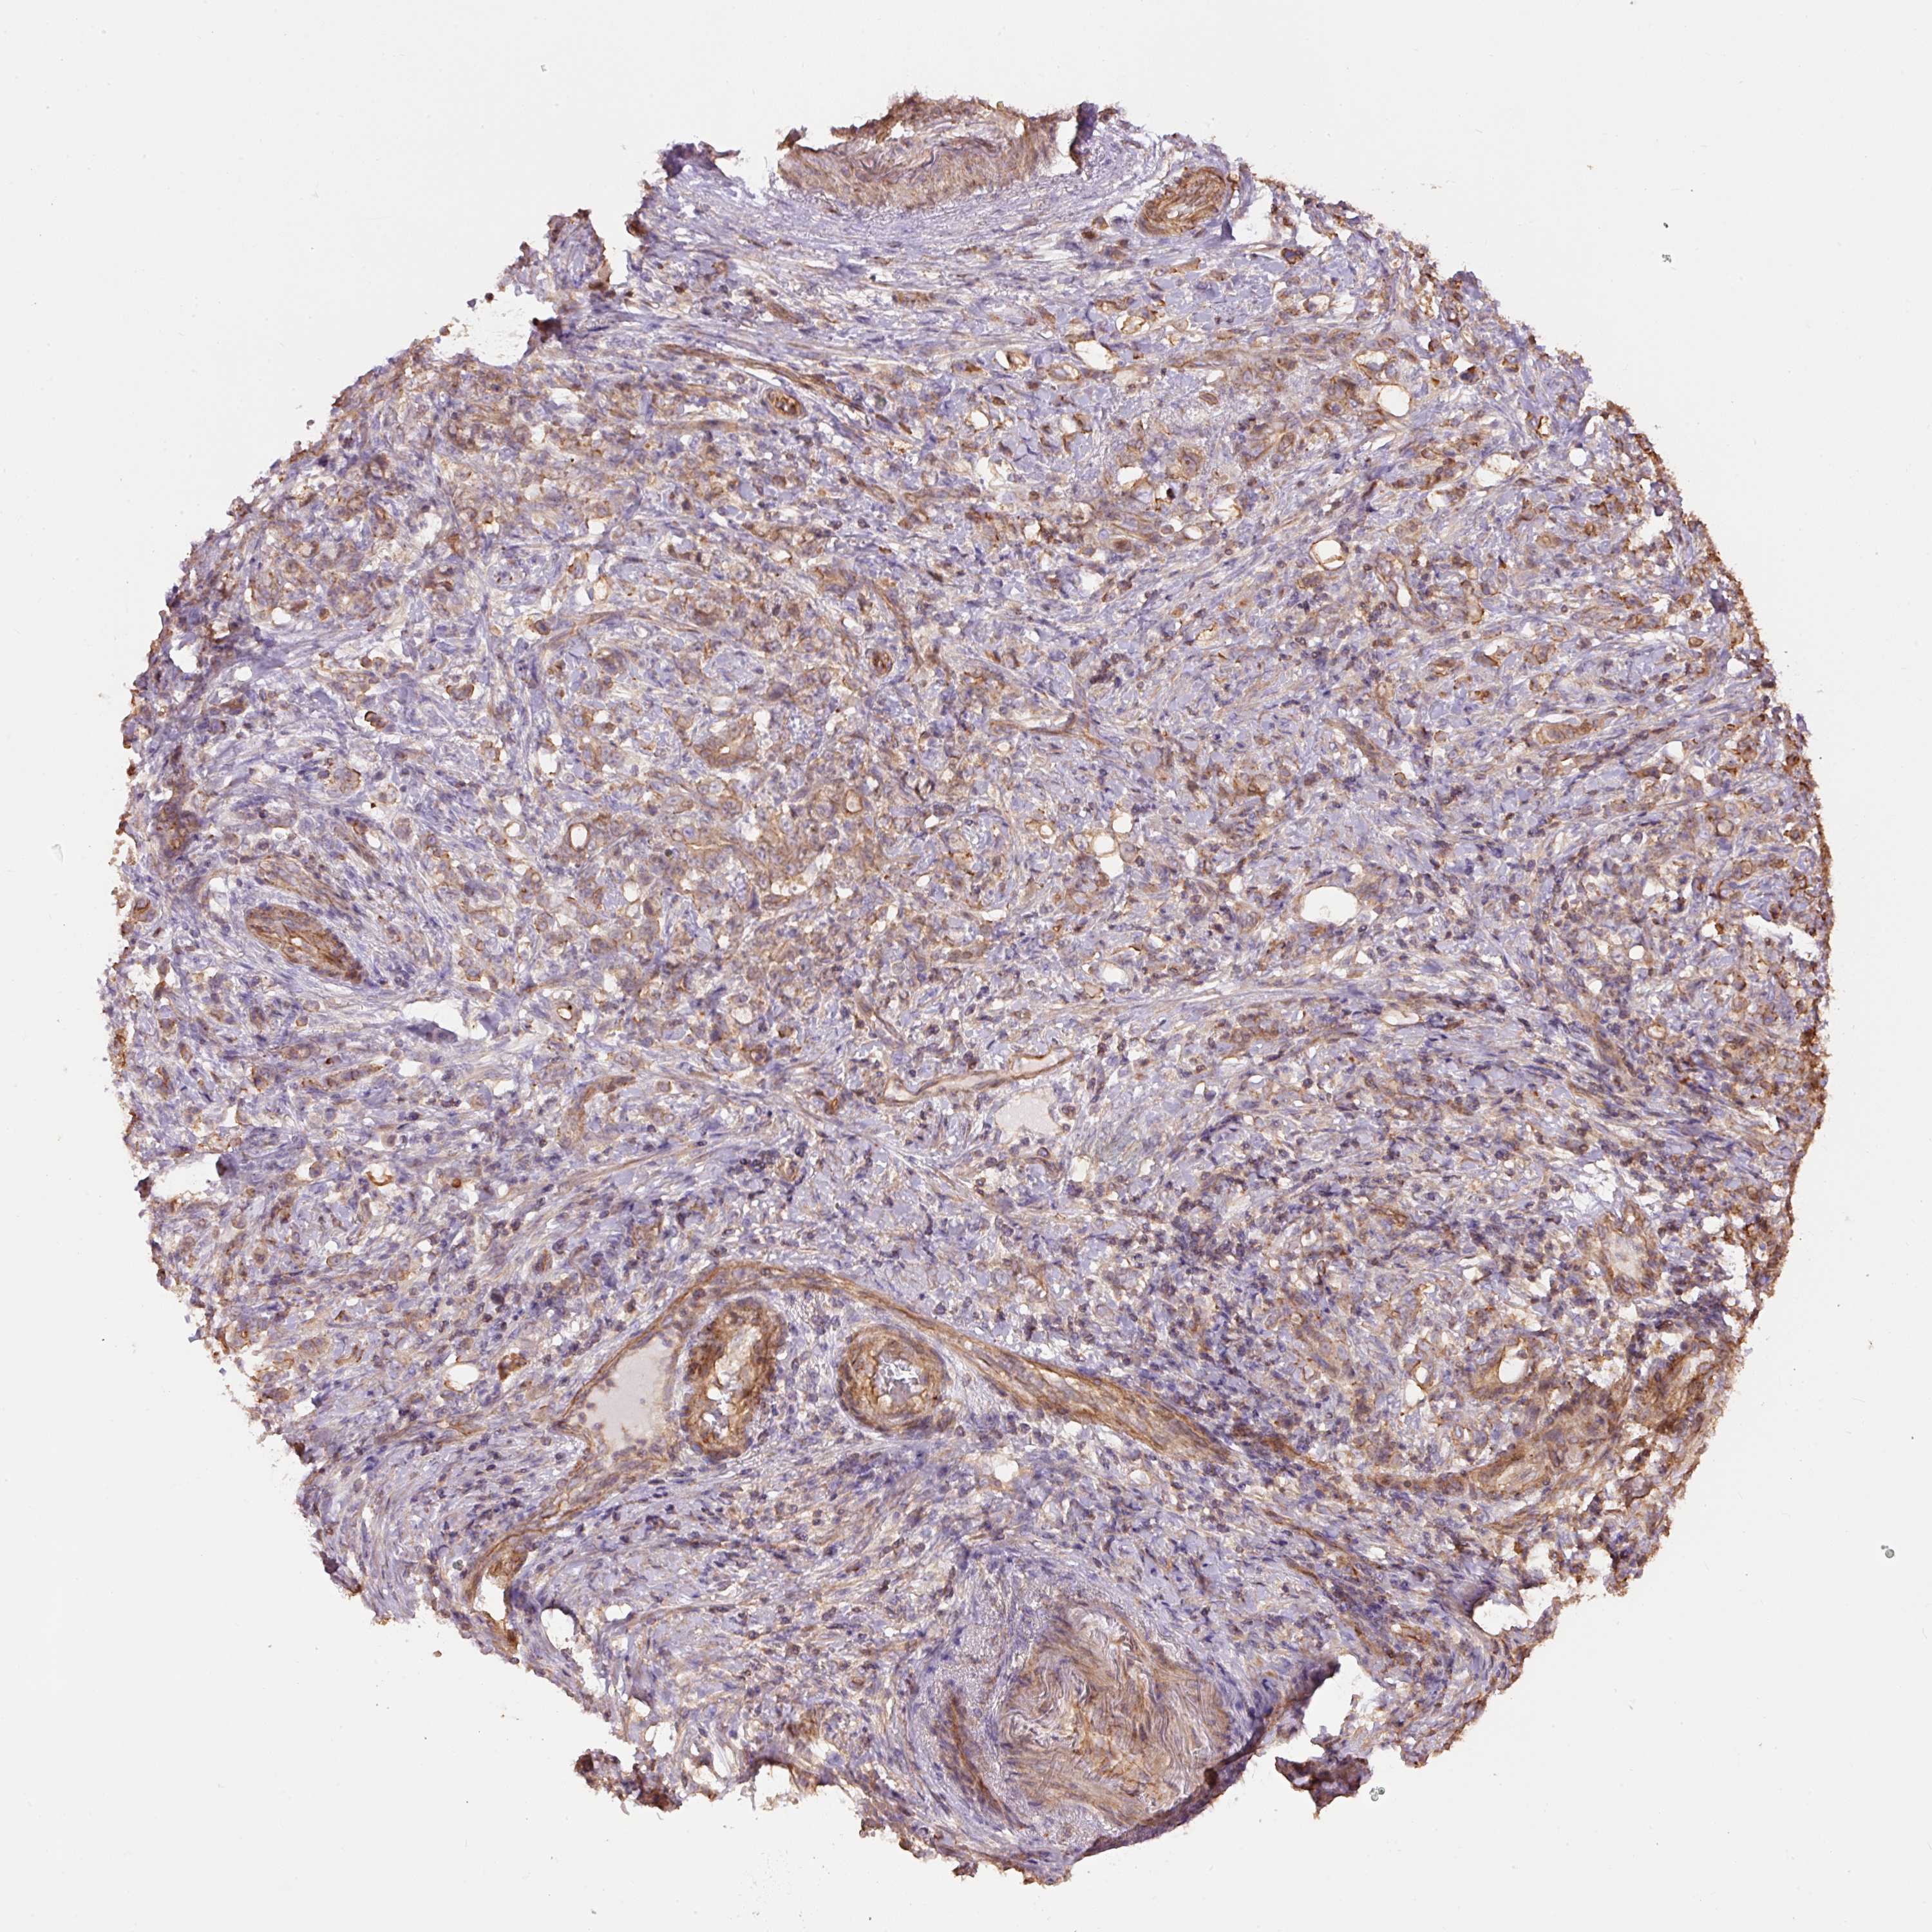

STOMACH CANCER - Protein expressioni

A mouse-over function shows sample information and annotation data. Click on an image to view it in a full screen mode. Samples can be filtered based on level of antibody staining by selecting one or several of the following categories: high, medium, low and not detected. The assay and annotation is described here.

Note that samples used for immunohistochemistry by the Human Protein Atlas do not correspond to samples in the TCGA dataset.

Antibody stainingi

Antibody staining in the annotated cell types in the current human tissue is reported as not detected, low, medium, or high, based on conventional immunohistochemistry profiling in selected tissues. This score is based on the combination of the staining intensity and fraction of stained cells.

Each image is clickable and will lead to virtual microscopy that enables deeper exploration of all samples and also displays staining intensity scores, fraction scores and subcellular localization as well as patient and tissue information for each sample.

Antibody HPA048630

Antibody HPA061142

Antibody CAB004026

Staining

High

Medium

Low

Not detected

Intensity

Strong

Moderate

Weak

Negative

Quantity

>75%

75%-25%

<25%

None

Location

Nuclear

Cytoplasmic/membranous

Cytoplasmic/membranous,nuclear

Adenocarcinoma, NOS

Adenocarcinoma, High grade